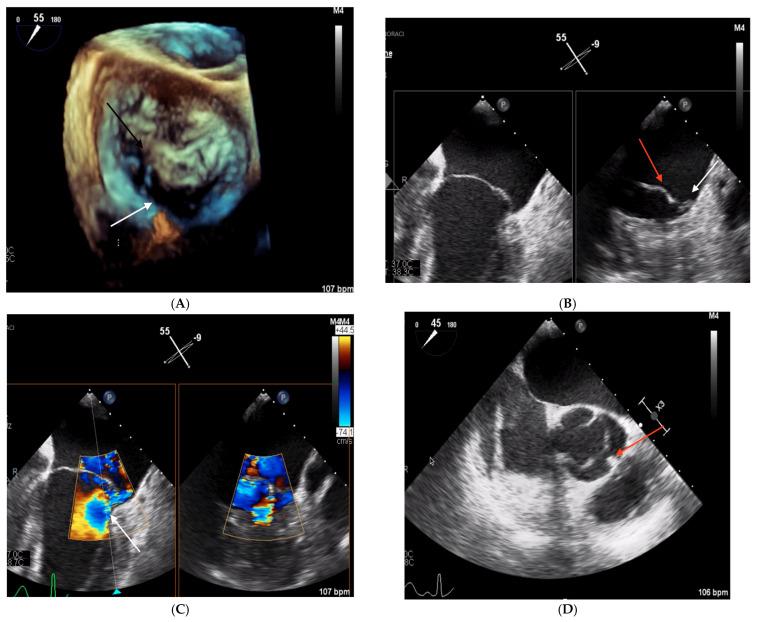

Posterior mitral leaflet hypoplasia is a rare condition, generally diagnosed in children. This paper presents three adult cases of posterior leaflet hypoplasia and comprehensively reviews the existing literature. All patients presented with severe mitral regurgitation necessitating hospitalization. Transthoracic and transesophageal echocardiography were performed to determine the underlying etiology, revealing pronounced posterior mitral leaflet hypoplasia. Each case was evaluated by a multidisciplinary heart team. Surgical mitral valve intervention was feasible in two patients. In one high-risk patient, percutaneous treatment options for MR were explored but ultimately deemed unsuitable due to the anatomical characteristics of the valve. The patient was consequently managed conservatively with medical therapy. These cases demonstrate that posterior mitral leaflet hypoplasia may constitute an underrecognized cause of severe primary mitral regurgitation in adults. The management of such cases can be particularly challenging due to the atypical valvular morphology.

二尖瓣后叶发育不全是一种罕见的病症,通常在儿童期被诊断出来。本文介绍了三例成人二尖瓣后叶发育不全的病例,并对现有文献进行了全面综述。所有患者均因严重二尖瓣反流而需要住院治疗。通过经胸和经食管超声心动图来确定潜在病因,结果显示二尖瓣后叶明显发育不全。每个病例均由多学科心脏团队进行评估。两名患者可行二尖瓣手术干预。在一名高危患者中,探讨了二尖瓣反流的经皮治疗方案,但最终由于瓣膜的解剖特征而认为不合适。因此,该患者接受药物保守治疗。这些病例表明,二尖瓣后叶发育不全可能是成人严重原发性二尖瓣反流的一个未被充分认识的原因。由于瓣膜形态不典型,此类病例的管理可能极具挑战性。